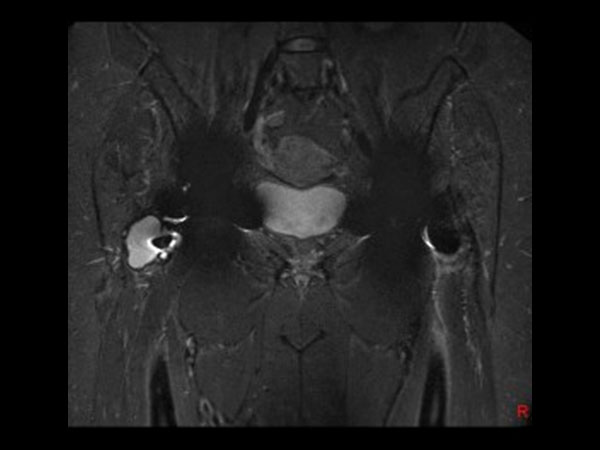

Coronal T1w TSE

Coronal T1w MARS